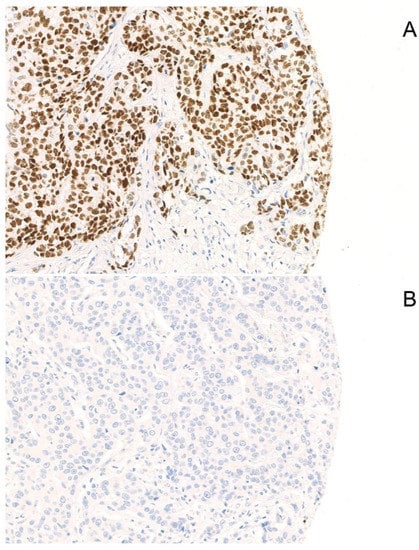

SOX-10 positivity was found in 46 (41%) patients, while 67 (59%) patients were negative. Typical examples of positive and negative staining are displayed in Figure 1.

Figure 1.

Examples of SOX-10-positive and -negative staining. A typical example of positive (A) and negative (B) nuclear staining of SOX-10 is displayed (Magnification: 200×).